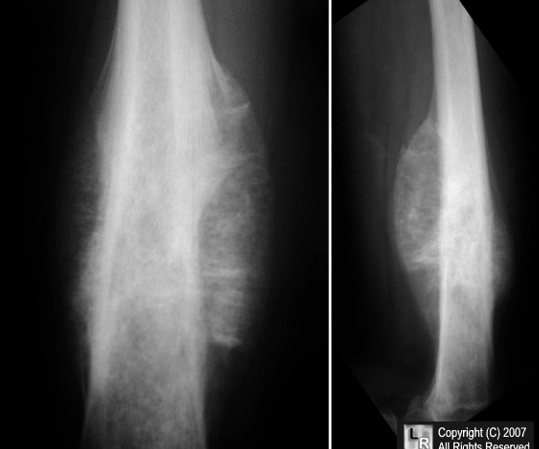

Legg-Calvé-Perthes disease

avascular necrosis of the femoral head

cause: Interruption of the blood supply by a currently unknown cause.

Demographics: Onset is usually between 2 and 12 years of age

symptoms: presents with a painless limp, although mild pain of the anterior thigh is common.,

Osgood-Schlatter

path: Repeated microfracture of the tibial tubercle at the insertion of the patellar tendon. This is an overuse injury

pt: young athletes

symptoms: presents with swelling and knee pain localized to the tubercle.

treatment: Improvement occurs with rest.,

Slipped capital femoral epiphysis (SCFE)

demographics: typically occurs in overweight adolescents or thin pt who had underwent rapid growth spurt

symptoms: presents with a limp. Pain when moving hips

labs: Radiographically, the capital femoral epiphysis is separated from the neck of the femur and remains in the acetabulum as the rest of the femur moves anteriorly.,